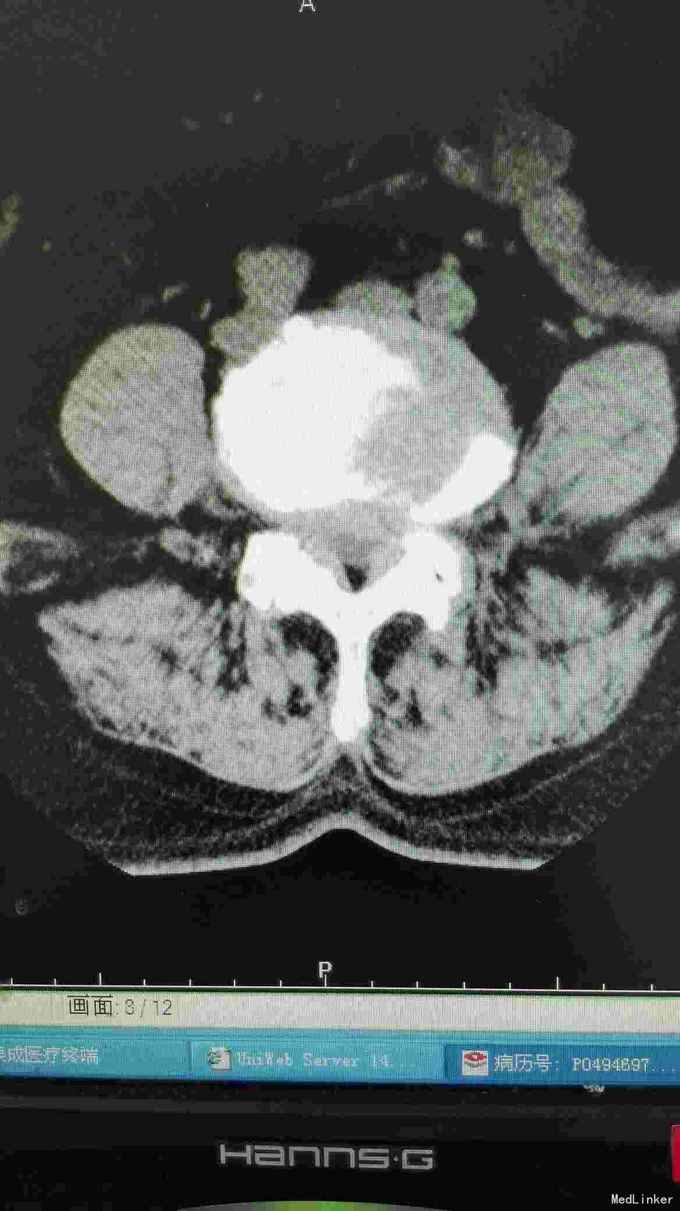

患者腰部疼痛伴右下肢疼痛麻木2年,间隙性跛行。

腰椎影像检查提示椎间盘突出,椎管狭窄,退变侧弯。

诊断腰椎间盘突出症,腰椎管狭窄症,腰椎退变性侧弯。 在全麻下行腰椎固定,减压,畸形矫正融合术。